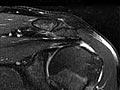

Magnetic resonance imaging (MRI) is a test done with a large machine that uses a magnetic field and pulses of radio wave energy to make pictures of the shoulder. Muscles, ligaments, cartilage, and other joint structures are best seen with an MRI. In many cases an MRI gives information about structures in the body that can't be seen as well with an X-ray, ultrasound, or CT scan.

For an MRI test, you are placed inside the magnet so that your shoulder is inside the strong magnetic field. An MRI can find changes in the structure of organs or other tissues. It also can find tissue damage or disease, such as infection or a tumor. Pictures from an MRI scan are digital images that can be saved and stored on a computer for further study. The images also can be reviewed remotely, such as in a clinic or an operating room. Photographs or films of selected pictures can also be made.

Magnetic resonance imaging (MRI) of the shoulder

Normal:

- The muscles, tendons, bones, and joints look normal in size, shape, and location.

- No growths, such as tumors, are present.

- No cartilage problems or tears, broken bones (fractures), or loose bodies are present.

- No rotator cuff injury or tear is present.

- No signs of inflammation or infection are present.

Abnormal:

- A growth, such as a tumor, inflammation, or infection in the bone or joint, is present.

- A collection of fluid is found, which could mean you have an infection.

- Damage to ligaments, tendons, or cartilage is present.

- Joint damage is present, and bones may show signs of disease or fracture.